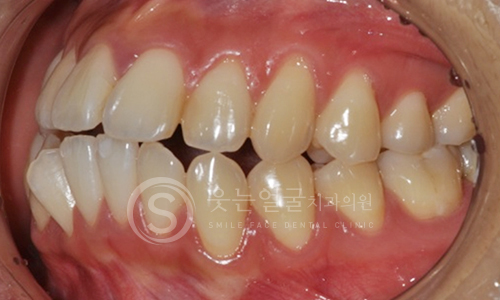

한눈에 보는

치아교정 전후사진